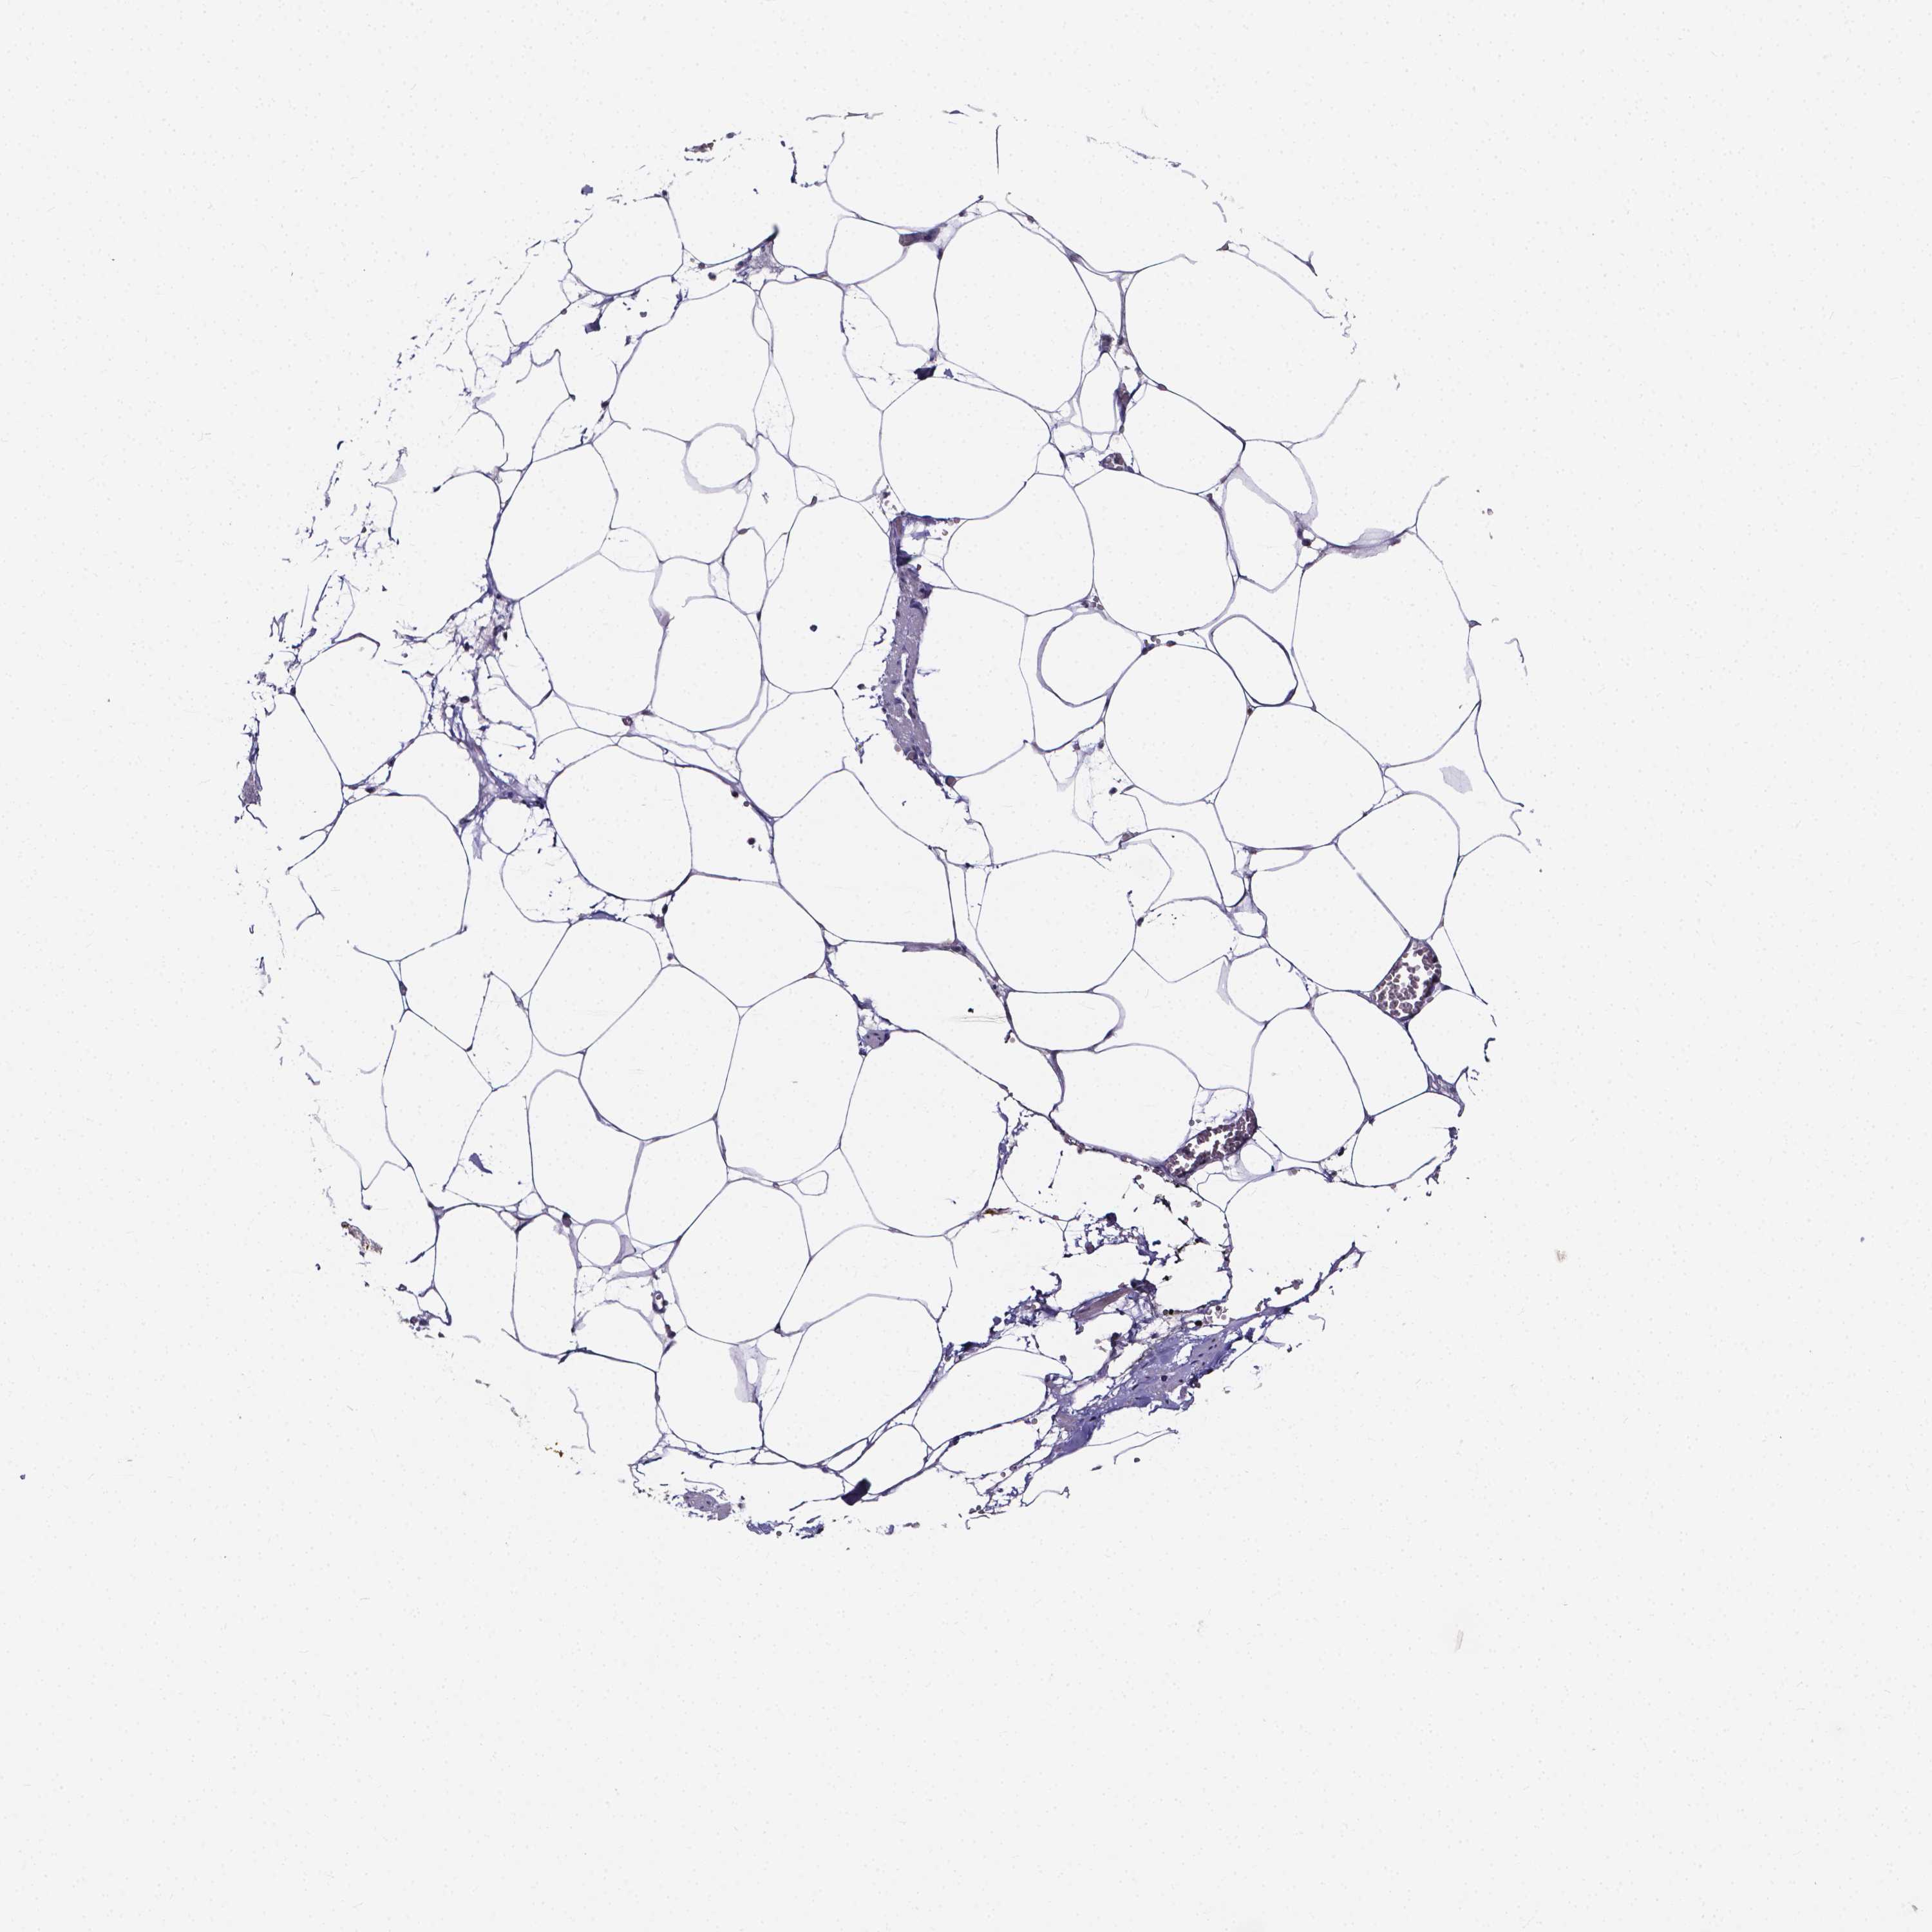

SOFT TISSUE 1 - Antibody stainingi

Antibody staining in the annotated cell types in the current human tissue is reported as not detected, low, medium, or high, based on conventional immunohistochemistry profiling in selected tissues. This score is based on the combination of the staining intensity and fraction of stained cells.

Each image is clickable and will lead to virtual microscopy that enables deeper exploration of all samples and also displays staining intensity scores, fraction scores and subcellular localization as well as patient and tissue information for each sample.

Antibody HPA031422Antibody HPA031425

Fibroblasts Not detectedNot detected

Peripheral nerve Not detectedNot detected